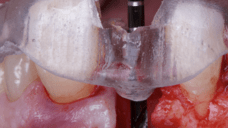

The surgical protocol began with the atraumatic extraction of tooth 1.1 to preserve as much of the alveolar socket as possible. Immediately following extraction, an N1 implant was placed into the socket using a guided surgical approach to ensure ideal three-dimensional positioning. The “one abutment one time” technique was applied to minimize soft tissue manipulation during the healing phase, which is particularly important in esthetic areas.

On the same day as the surgery, an immediate-load provisional crown was delivered. This restoration was fabricated in acrylic resin and screw-retained on the implant, following the “one abutment one time” principle. The provisional crown was carefully adjusted to avoid occlusal loading while supporting the peri-implant soft tissue architecture during the healing phase.

After an appropriate healing period, the definitive prosthesis was planned and delivered. A screw-retained zirconia crown was fabricated to ensure long-term durability, optimal esthetics, and retrievability. Zirconia was selected for its mechanical strength and excellent esthetic properties, blending seamlessly with the adjacent natural dentition in both form and color.

The final crown was designed to maintain the gingival architecture that had been shaped by the provisional. Special attention was paid to the emergence profile, contact points, and translucency to achieve harmony with the patient’s smile. The definitive restoration provided functional stability and esthetic integration, fulfilling the patient’s expectations for a fixed and natural solution.